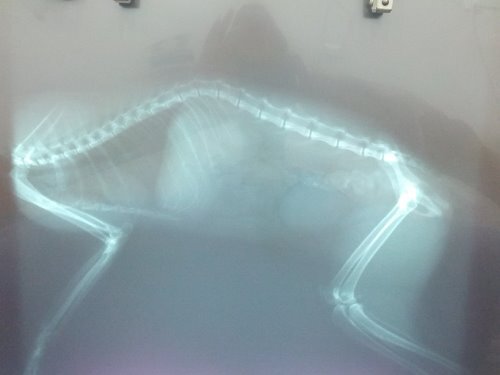

主題: 下半身癱瘓~求助 申請者姓名: Jason Yang 花色: 申請日期: 2013-06-07 00:05:28 申請者部落格: 申請者臉書網址: 所在縣市/合作醫院: 新北市/哲生動物醫院 治療費用: 6200元 需求人數: 8人 已結案 (2013-08-06 14:01:08) 報名人員: Chloe Liang(已付款)、alicelin(已付款)、Sean Chun-hsiang Yo、貓球球(已付款)、himawari(已付款)、himawari、himawari、Bei Yi Su(已付款)、Fei Lika Tsai(已付款)、Fu Nk(已付款)、Yvonne Chen(已付款)、 候補人員: 動物病情說明: 在我的工廠發現一隻玩到下半身不能動的貓,於晚上九點多發現,已詢問淡水之上哲動物醫院該如何處置~目前餵食罐與與放置鐵籠~已鋪設毛毯及紙箱~~明日將帶前往醫院檢查是否有救...

貓目前意識清楚~唯有腳~尾巴無法動作

貓咪檢查後發現第一薦椎骨折,造成後半身癱瘓,眼睛也有病變,經過六天治療,貓咪都不願意自己進食,精神很差,每天醫師都有幫他擠尿按摩腹部幫助他排便,治療不見改善,幾經考量,為減輕貓咪的痛苦,只好以人道的方式送貓咪一程,還請各位幫忙貓咪。謝謝!